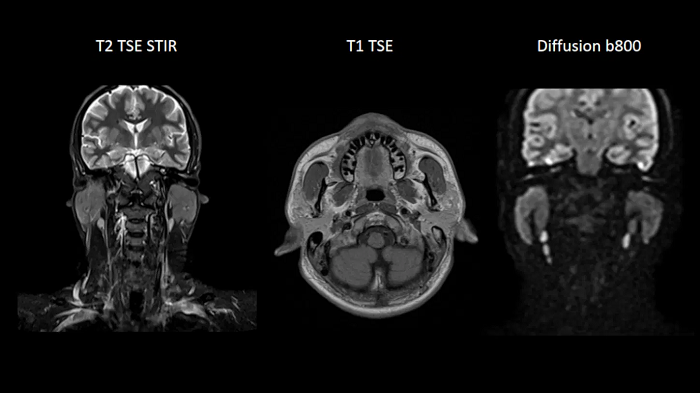

Neck

Excellent soft tissue contrast in the neck

An all-inclusive soft tissue investigation in the head with outstanding image quality for T1, T2, and diffusion contrast.

MAC-ID: 7aaaa0158. Image Credit: Siemens Healthineers